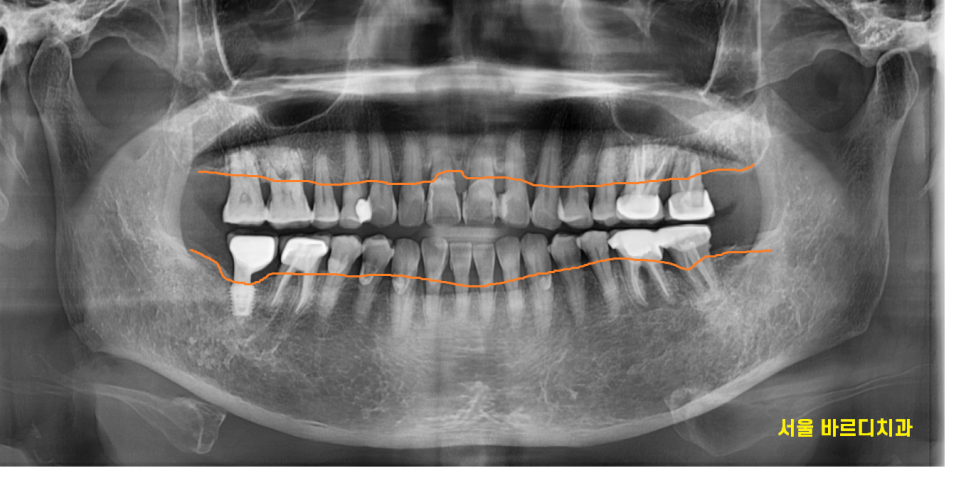

위 큰어금니 흔들림

이가 흔들려 내원한 환자분입니다.

치아가 흔들린다는 것은

엑스레이를 찍어보지 않아도

아.. 잇몸이 안좋으시겠구나

예측할 수 있었는데요.

역시나 잇몸뼈가 많이 내려간 것을 확인하였습니다.

23.09.26

그중에서도 왼쪽 맨 끝에 치아가 심각했습니다.

뿌리를 감싸고 있는 뼈가

까맣게 보이네요~

염증으로 많이 녹기도 하였고

어금니 흔들림을 동반한 통증

느끼실만큼 많이 상하였습니다.